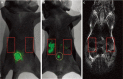

Breast cancer (BC) is a serious disease to threat lives of women. Numerous studies have proved that BC originates from cancer stem cells (CSCs). But at present, no one approach can quickly and simply identify breast cancer stem cells (BCSCs) in solid tumor. Nanotechnology is probably able to realize this goal. But in study process, scientists find it seems that nanomaterials with one modality, such as magnetic resonance imaging (MRI) or fluorescence imaging (FI), have their own advantages and drawbacks. They cannot meet practical requirements in clinic. The nanoprobe combined MRI with FI modality is a promising tool to accurately detect desired cells with low amount in tissue. In this work, we briefly describe the MRI and FI development history, analyze advantages and disadvantages of nanomaterials with single modality in cancer cell detection. Then the application development of nanomaterials with dual-modality in cancer field is discussed. Finally, the obstacles and prospective of dual-modal nanoparticles in detection field of BCSCs are also pointed out in order to speed up clinical applications of nanoprobes.